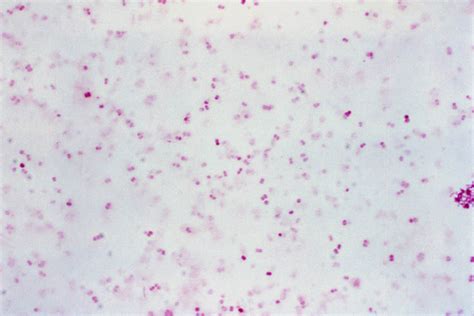

Identifying Gram Neg Diplococci involves several laboratory techniques. The Gram stain is the initial step, where the bacteria appear as Gram-negative, round, or oval-shaped cells in pairs. Further identification can be done using biochemical tests, serological tests, and molecular methods.

Biochemical tests involve growing the bacteria on specific media and observing their metabolic activities. For example, Neisseria gonorrhoeae can be identified by its ability to ferment glucose but not maltose or sucrose. Serological tests use antibodies to detect specific antigens on the bacterial surface. Molecular methods, such as polymerase chain reaction (PCR), can detect the genetic material of the bacteria, providing a highly specific and sensitive identification.